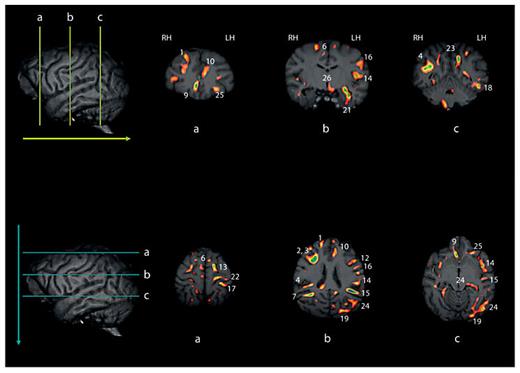

Sagittal views of the left (LH) and right (RH) hemispheres at different planes of depth. The color bar indicates the variation in t values corresponding to asymmetries in the different white matter clusters.

Sagittal views of the left (LH) and right (RH) hemispheres at different planes of depth. The color bar indicates the variation in t values corresponding to asymmetries in the different white matter clusters.

White matter asymmetries projected onto a 3D chimpanzee brain at different parasagittal levels are shown in figure 1. As can be seen, there are pronounced leftward asymmetries, particularly within the temporoparietal and frontal regions. In total, 27 significant clusters were identified by the VBM analysis. The regions and their x, y, z coordinates are shown in table 1. Leftward asymmetries were found for 18 regions and rightward asymmetries were found for 9 regions. Within the left hemisphere, asymmetries were present in several main gyri including the occipital gyri (clusters 19, 20), angular gyrus (cluster 24), postcentral gyrus (clusters 16, 17), precentral gyrus (clusters 12, 22) and the middle and superior frontal gyri (clusters 11, 13). Several white matter asymmetries were also found in regions corresponding to well-know tracts within the human brain including the superior longitudinal fasciculus (clusters 14, 18), inferior frontooccipital fasciculus (clusters 15, 21), inferior longitudinal fasciculus (cluster 18) and uncinate fasciculus (cluster 21). Within the right hemisphere, asymmetries were also found in superior and middle frontal gyri (clusters 1, 6) as well as in the inferior frontal gyrus (cluster 3), and superior parietal lobe (cluster 5). Asymmetries in tracts corresponding to the superior longitudinal fasciculus (clusters 3, 4) and inferior frontooccipital fasciculus (cluster 7) were also found within the right hemisphere fig. 2.

Upper and lower panels reflect selective coronal (upper) and axial (lower) views of the different white matter cluster revealed by VBM. The numbers in each corresponding image reflect the cluster identified in table 1. Note, some clusters are unlabeled and in these cases, the clusters are visible on the single slice shown in the image, but the size of the cluster when considered across multiple slices may not have reached our size criterion (see text for description). LH = Left hemisphere; RH = right hemisphere.

Upper and lower panels reflect selective coronal (upper) and axial (lower) views of the different white matter cluster revealed by VBM. The numbers in each corresponding image reflect the cluster identified in table 1. Note, some clusters are unlabeled and in these cases, the clusters are visible on the single slice shown in the image, but the size of the cluster when considered across multiple slices may not have reached our size criterion (see text for description). LH = Left hemisphere; RH = right hemisphere.